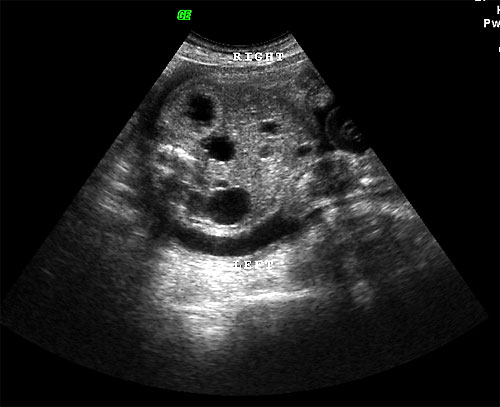

- Mild renal pyelectasis